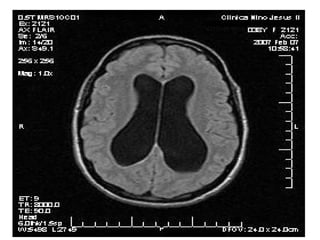

Absceso cerebral IRM

El diagnostico se establece mediante RM. Es

fundamental llevarlo acabo en los primeros estadios.